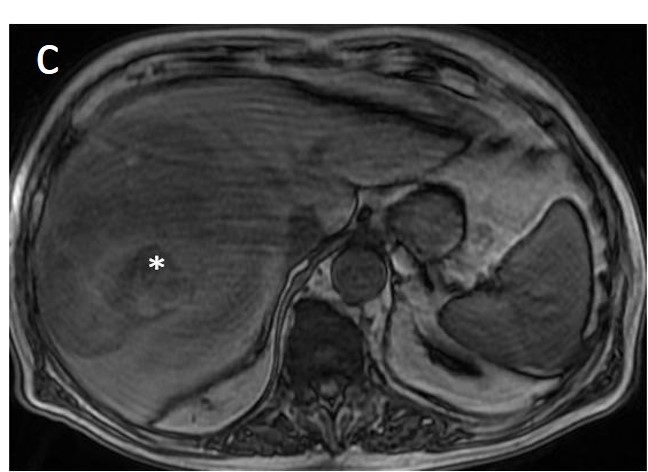

Figure 12. A large HCC is depicted in the right liver lobe of this 81-year-old man. The tumor is surrounded by a capsule, nicely seen as a thin, low signal line on the fat-suppressed T2 sequence (arrowheads) (a) and shows inhomogeneous but predominantly high T2 signal intensity. Areas of fat are clearly shown in the in/out of phase images (asterisk) (b,c). This marked heterogeneity is known as the “mosaic” pattern. After contrast administration, mottled arterial enhancement is noted (d); definite wash-out and capsular enhancement (arrows) are seen on the portal phase (e).

The presence of a capsule (Figure 12) is a major finding according to LI-RADS, but not EASL. The capsule is a characteristic feature of progressed HCC and is absent in dysplastic nodules or early HCCs. It shows low T1 and T2 signal intensity and enhancements on the portal and delayed phase at 3 min after contrast injection (or transitional phase if hepatospecific contrast agent is used); on the contrary, corona enhancement occurs earlier on the arterial phase. A capsule should be thicker than the fibrous septa of cirrhosis, which also show delayed enhancement. An intact capsule on imaging has been associated with lower recurrence rates after treatment [137], while extracapsular tumor extension predicts poor survival [138]. It should be stressed, however, that an encapsulated progressed HCC has a worse prognosis than an unencapsulated early HCC; the presence of a capsule confers a better prognosis only when the encapsulated tumor is compared to HCCs of a similar size and grade with breached capsules or without a capsule.

Fatty change is encountered in approximately 40% of early HCCs [143]. With increasing tumor size and histologic grade, fat usually regresses and the percentage drops to 6% in moderately-differentiated HCCs [144], only to increase again in highly de-differentiated tumors. This occurs along with the diminished arterial supply, suggesting a connection between reduced blood flow, hypoxia, and steatogenesis [145]. MRI is superior to CT in detecting fatty change with the use of chemical shift sequences, which show the characteristic signal drop on the opposed-phase compared to the in-phase (Figures 12 and 13). Intratumoral fat can also be used to exclude cholangiocarcinoma, which is also associated with cirrhosis. Nevertheless, the added value of fat identification in a HCC is debatable because, when detected, other more suggestive features (like the vascular pattern) are already present [123].

When a smaller nodule is seen within a larger nodule, it implies de-differentiation of a cell subpopulation and progression towards hepatocarcinogenesis. The “nodule-in-nodule” sign suggests development of HCC within a dysplastic nodule (Figure 13) and the typical HCC features, such as the wash-in/wash-out pattern or diffusion restriction, are seen in the inner nodule. When numerous foci with different imaging characteristics are seen within a nodule, the appearance is known as a “mosaic” pattern and is usually encountered in large tumors (Figure 12), thereby facilitating the differentiation from cholangiocarcinoma [54].